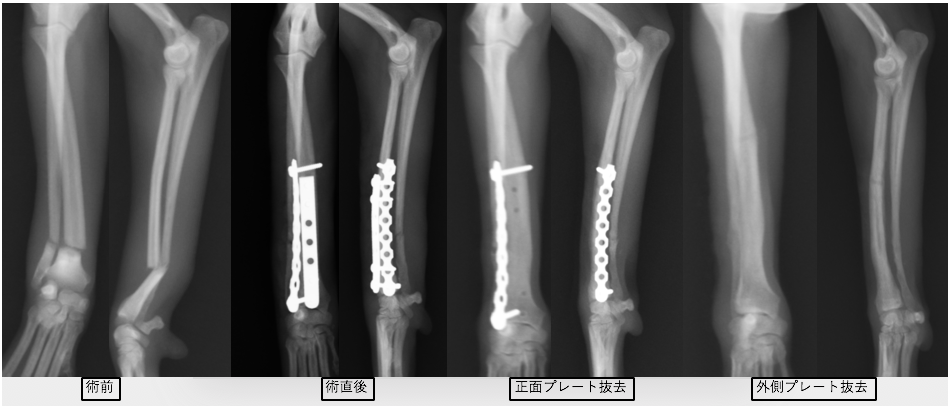

近年、小型犬が増加しているのに比例して橈尺骨骨折が増加しています。橈尺骨骨折にはプレートを2枚入れる方法を用います。2枚入れることで強度を増すことができプレートの破綻を防止できます。また、1枚ずつプレート抜去が可能であるため、ある程度骨が固まってきたら1枚抜去し、さらに骨化を促進し、もう一枚抜去するという方法が可能です。そうすることで癒合不全(骨化が遅れること)を防止し、プレート抜去後の再骨折のリスクを減らすことができます。

当院ではピンやロッキングプレートなどは抜かない場合もありますが、基本的にはプレートスクリューはなるべく抜去してきちんと骨癒合していることを確認して終了としています。

術後レントゲンです。橈骨全域に渡ってプレートが入っています。近位は少し外側に曲がっているため、最初からプレートを曲げています。術後2日目には患肢を使っての歩行が可能でした。また、キャスト(ギプス)も使わないので、ストレスなく生活が可能です。術後1ヶ月半ほどで正面のプレートを抜去しています。

この子もプレートが破綻して2回めの手術をしているため、プレートが長くなっています。

術後経過は順調で2ヶ月ほどで正面のプレートを抜去しました。